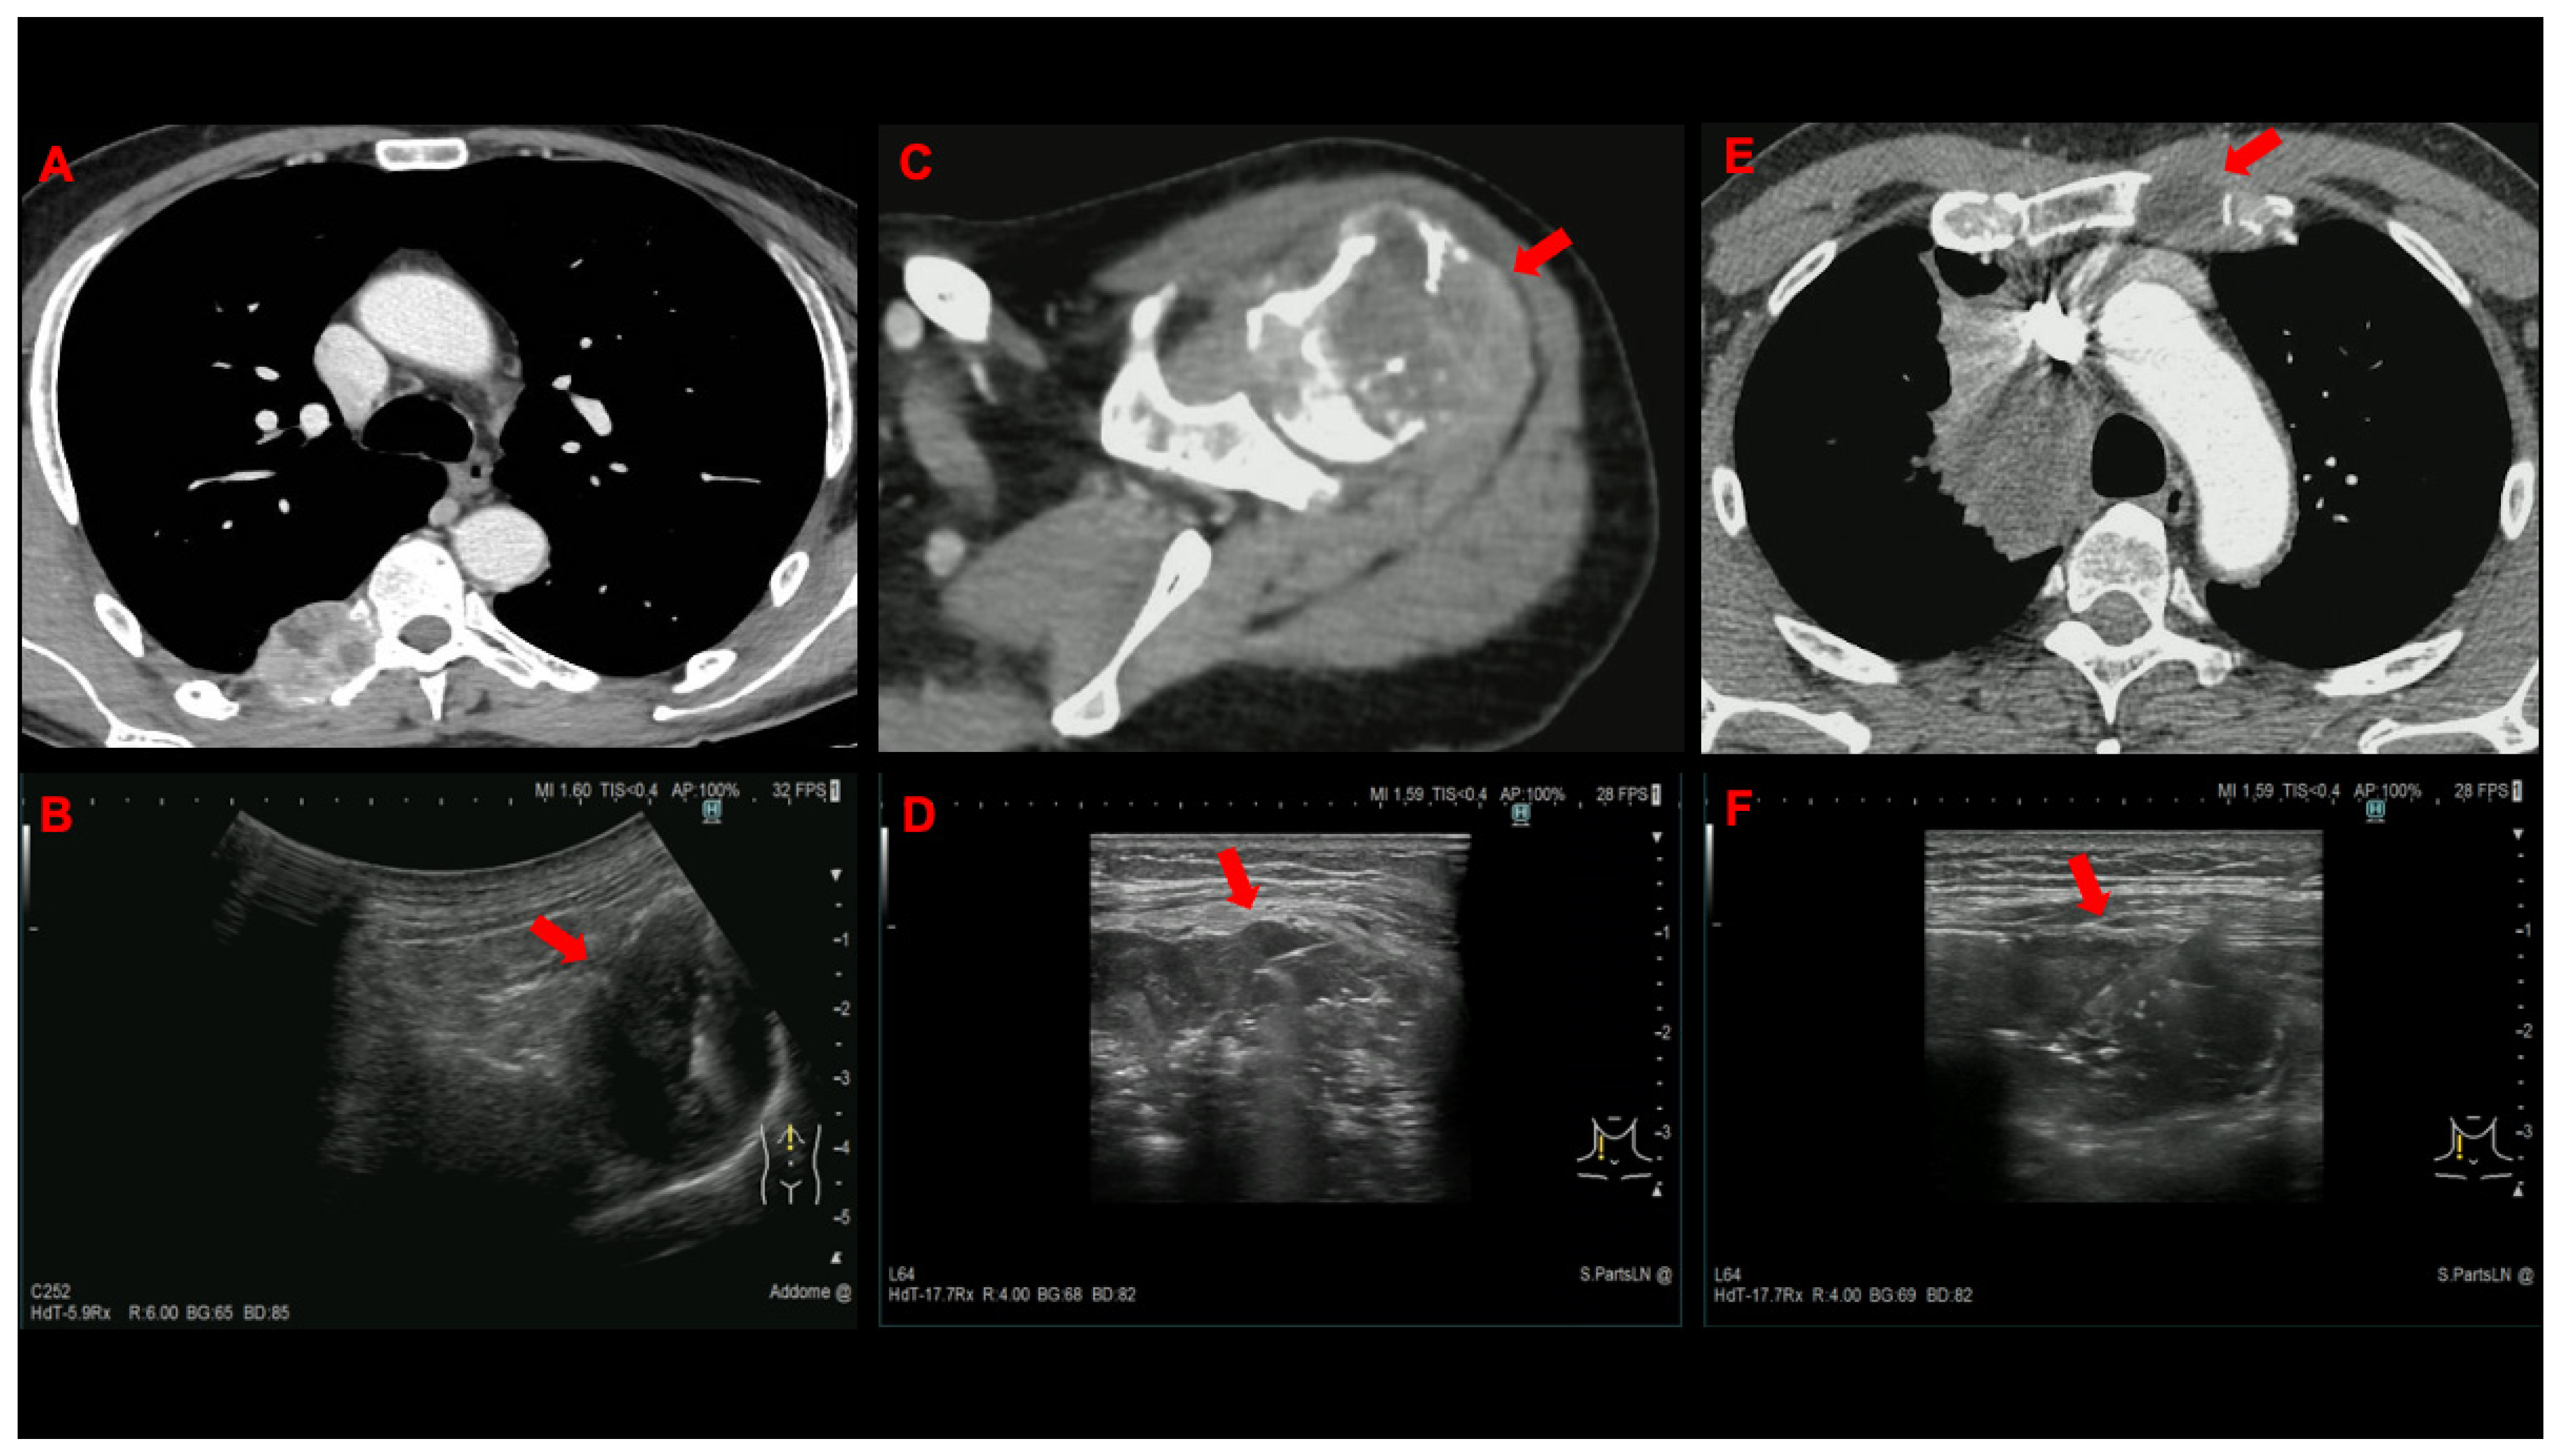

| Metastatic site, n. (%) | ||

| Lymph node | 54 (75) | 49 (68) |

| Supraclavicular | 44 | 40 |

| Cervical | 8 | 7 |

| Axillary | 2 | 1 |

| Mammary | 0 | 1 |

| Bone | 7 (9.7) | 11 (15.3) |

| Subcutaneous tissue | 6 (8.3) | 6 (8.3) |

| Thoracic wall | 3 (4.2) | 3 (4.2) |

| Muscle | 2 (2.8) | 1 (1.4) |

| Pleura | 0 (0) | 2 (2.8) |

| Study Group | Age/Sex | Lesion Location | No. Lesions Sampled | Needle Used | Tissue Core Retrieved | Final Diagnosis | |

|---|---|---|---|---|---|---|---|

| #1 | ROSE | 77/M | LN | 1 | 18G | No | NSCLC NOS |

| #2 | ROSE | 73/M | LN | 1 | 22G | No | SQCC |

| #3 | ROSE | 66/F | LN | 2 | 18G | Yes | Adenocarcinoma |

| #4 | ROSE | 48/M | LN | 2 | 22G | No | Adenocarcinoma |

| #5 | US-NAB | 66/F | LN | 1 | 18G | Yes | Adenocarcinoma |

| #6 | US-NAB | 86/M | Bone | 1 | 18G | Yes | Adenocarcinoma |